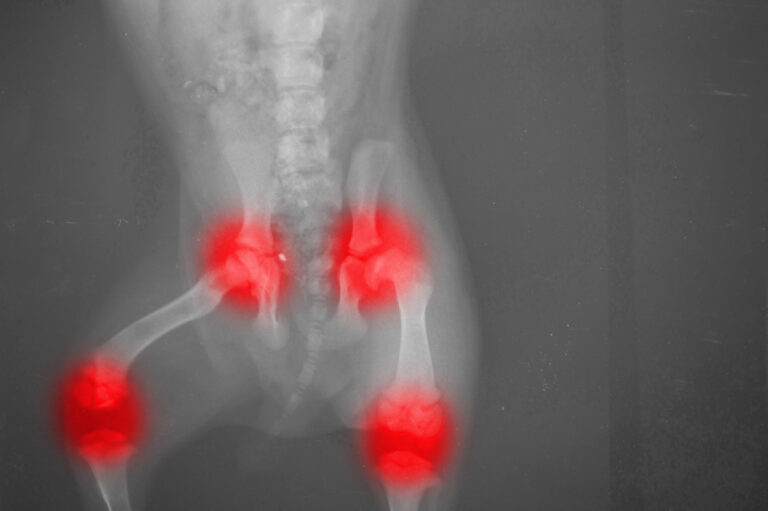

Your pet’s joints are formed by the ends of two bones coming together, held in place by ligaments that allow for whatever movement that particular joint needs. Because bones are hard and unyielding, they need a cushion between them to absorb impact and allow for a smoother movement than bones alone would be able to produce. This cushioning is provided by articular cartilage (articular means relating to a joint), which covers the bones and keeps them from rubbing together. When a pet has arthritis, that cartilage is breaking down, exposing highly sensitive areas that are being irritated every time the joint moves. There can be other effects, like the formation of extra bone called osteophytes, but the cartilage damage is the primary source of pain.

This damage can be caused by a few different things, but the two most common are trauma and obesity. The cartilage is designed to hold up against the normal, every day forces that the joint comes into contact with. When those forces exceed that amount, as they do in an injury, the cartilage can become damaged. Along with injury, the force of carrying too much weight can cause cartilage to break down, even if there are no other injurious forces on the joint. Over time, the pressure of the excess pounds can cause the cartilage to wear away, exposing the painful subchondral layer. Another cause is a skeletal malformity, such as hip and elbow dysplasia, causing the joint to move abnormally and put excess pressure in one area or another.

When this happens, the most common thing owners will see is stiffness, especially after the pet has been lying down for a while, and/or lameness in one or more limbs. There will sometimes be a crunching or grinding sound (called crepitus) when the joint moves, which is typically caused by gas invading the damaged tissues. These problems typically spread to both sides of the body, because when the pet shifts weight off of the damaged limb, they are placing excess pressure on the healthy side, leading to arthritis developing there as well. These symptoms can be relatively mild, but in advanced cases, they can be debilitating, resulting in so drastic a decrease on quality of life that it results in euthanasia. It is heartbreaking—for medical personnel, but more especially for owners—to have to end the life of an otherwise healthy pet because of uncontrollable pain.